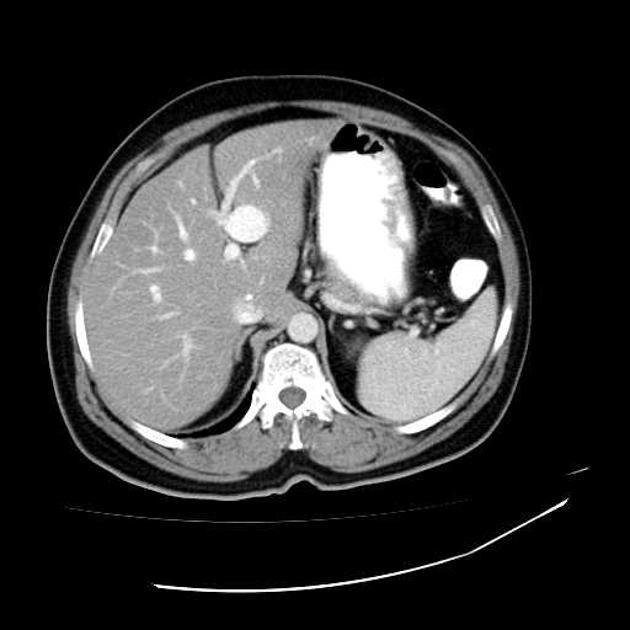

• Thay đổi đậm độ gan thoáng qua trên CT (Transient hepatic attenuation differences - THADs)

• Tăng áp lực tĩnh mạch cửa (Portal Hypertension)